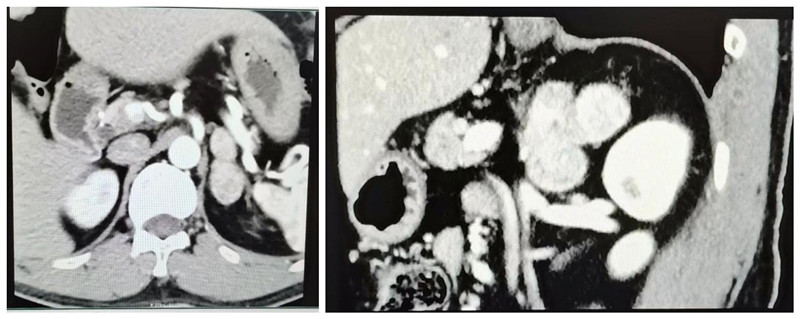

48岁男性患者,因体检发现左侧肾上腺占位20年,近年来多次院外就诊,建议手术切除肿瘤,但患者担心手术风险和术后肾上腺功能不足等问题,迟迟未能下定决心。此次在家人的建议下入住广西科技大学第一附属医院泌尿外科。入院后完善CT等检查提示左侧肾上腺肿瘤,大小约5.6×4.0cm,考虑嗜铬细胞瘤可能性大,有明确手术指征。

手术由泌尿外科吴尔岸主任医师主刀,考虑患者肿瘤偏大,瘤体与肾动静脉、胰尾、脾脏等关系密切,选择经腹入路,整个医师团队密切配合,依次分离显露出肾上腺及周围血管脉并将其夹闭,完整切除肾上腺及其肿瘤,手术过程少量出血,术中患者血压波动巨大,收缩压最高达240mmHg,最低达60mmHg,在麻醉科曾金主任团队努力配合下,手术过程有惊无险,得以顺利完成。术后患者恢复良好,康复出院。病理结果为嗜铬细胞瘤。